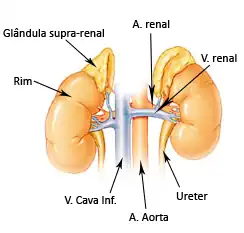

Para compreender melhor mediante a Hiperplasia Adrenal Congênita, é interessante entender a fisiologia e anatomia mediante a glândula envolvida, a adrenal, e se de interesse do leitor, aprofundar sobre o sistema endócrino.

Como ilustrada na imagem.